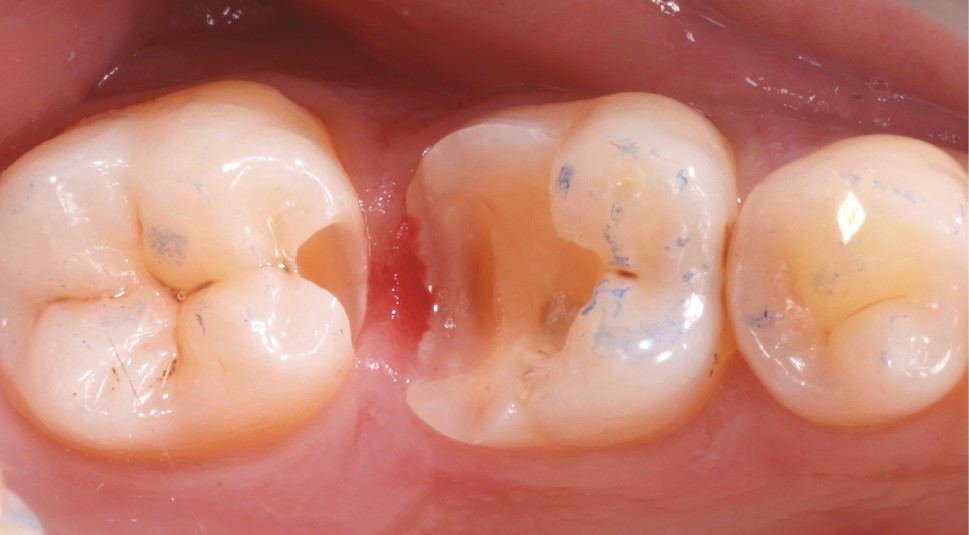

Lors de la préparation d’une cavité pour inlay/onlay, il est fréquent d’être confronté, en fin de nettoyage, à la présence d’une ou plusieurs parois résiduelles dont la résistance mécanique paraît douteuse du fait de leur localisation ou de leur épaisseur. Les parois épaisses (+ de 2 mm) peuvent généralement être conservées (cas clinique 1) et les parois fines (- de 1 mm) doivent généralement être recouvertes. Un inlay (en composite ou en céramique) est alors réalisé. Il doit avoir lui même, au final, une épaisseur globale minimale de 2 mm pour assurer sa résistance mécanique intrinsèque à la mastication. Si un recouvrement cuspidien est indiqué, la réduction occlusale doit donc se faire sur 2 mm de hauteur au minimum [1, 2].

Mais qu’en est-il des parois résiduelles d’épaisseur intermédiaire (entre 1 et 2 mm) (cas clinique 2) ?